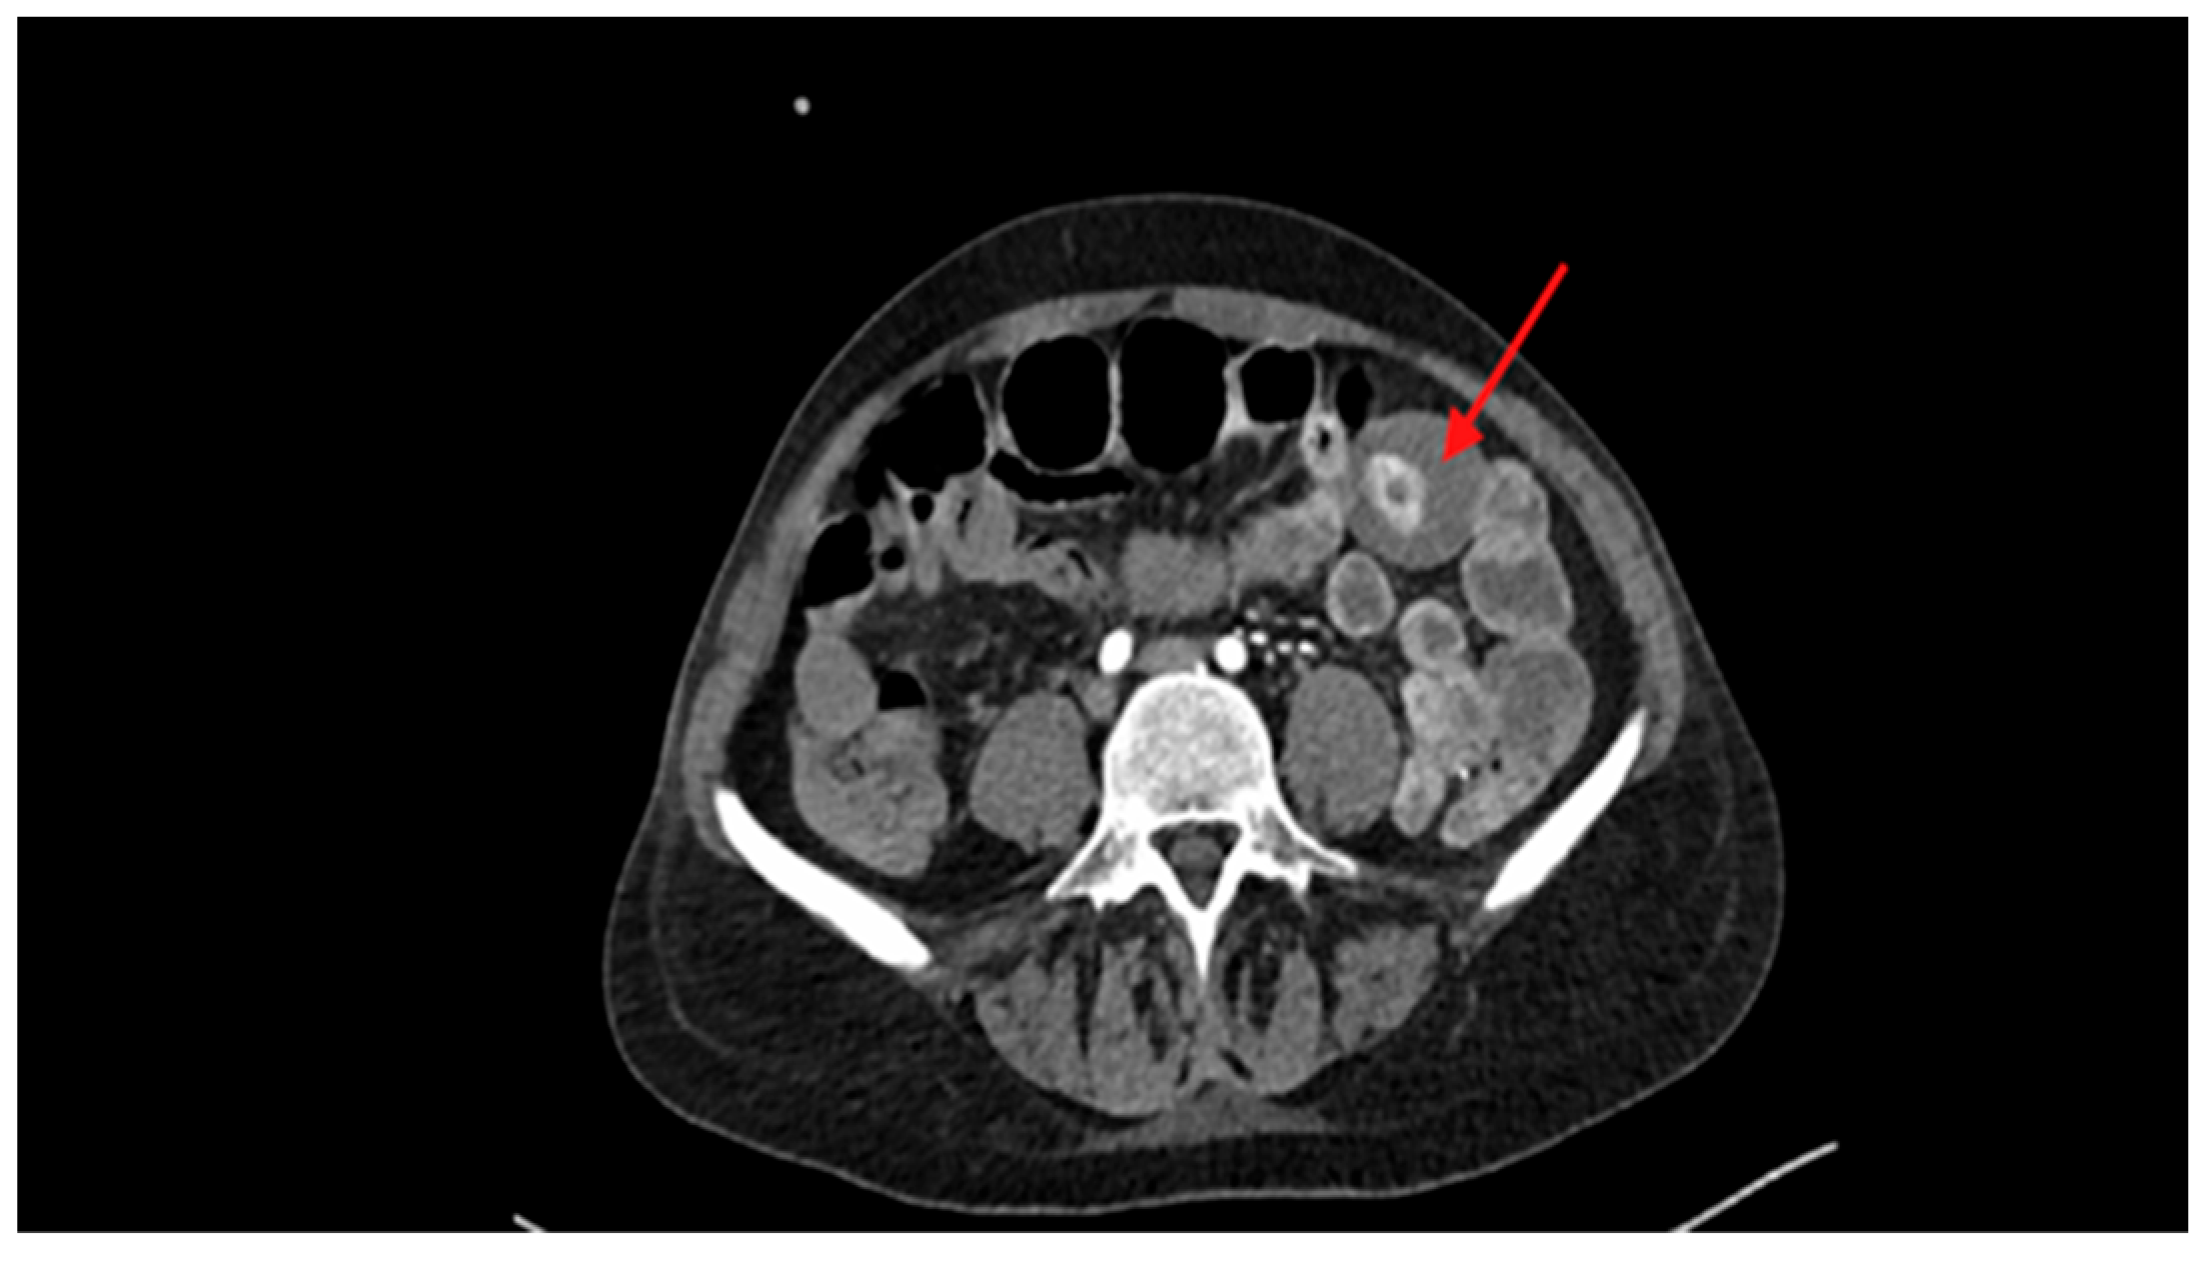

| Day 0—H20:45 | CT scan | Hyperdense intraluminal lesion in the small intestine, suspicious of bleeding lipoma. |